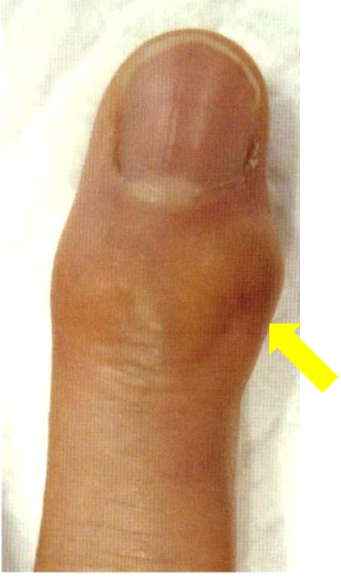

手・指のお悩み